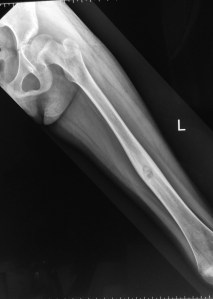

X-rays of the left femur showed the characteristic nidus surrounded by a zone of reactive bone.